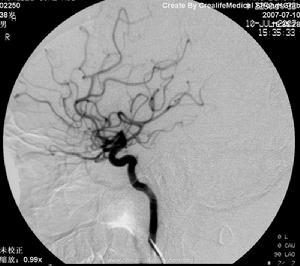

溶栓治疗有静脉溶栓及动脉溶栓治疗,对于大血管(如大脑中动脉、基底动脉、颈内动脉等)的急性闭塞,动脉内接触性溶栓效果更好,动脉再通率更高。动脉内接触性溶栓可以超选择性局部灌注溶栓药物方法,还行机械粉碎血栓。